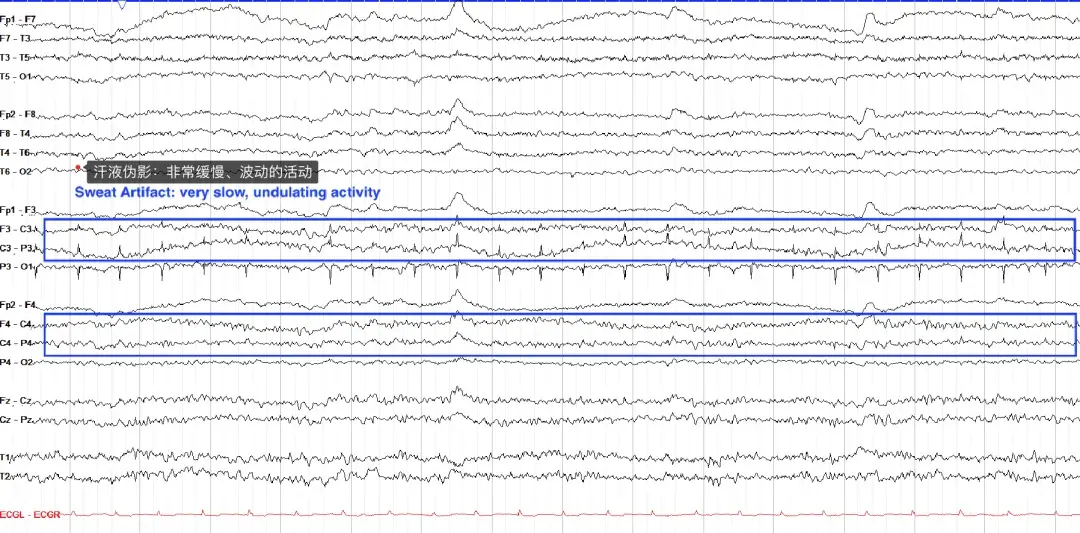

汗液伪影的特点是非常缓慢(通常小于 0.5 Hz)、相对较低的振幅活动,这是因为汗液中的氯化钠携带电荷,被 EEG 电极拾取。汗液伪影在定位方面不必遵循特定模式,可以是双侧、单侧,甚至仅集中于几个电极。下面的示例在 P3 处也有电极伪影。